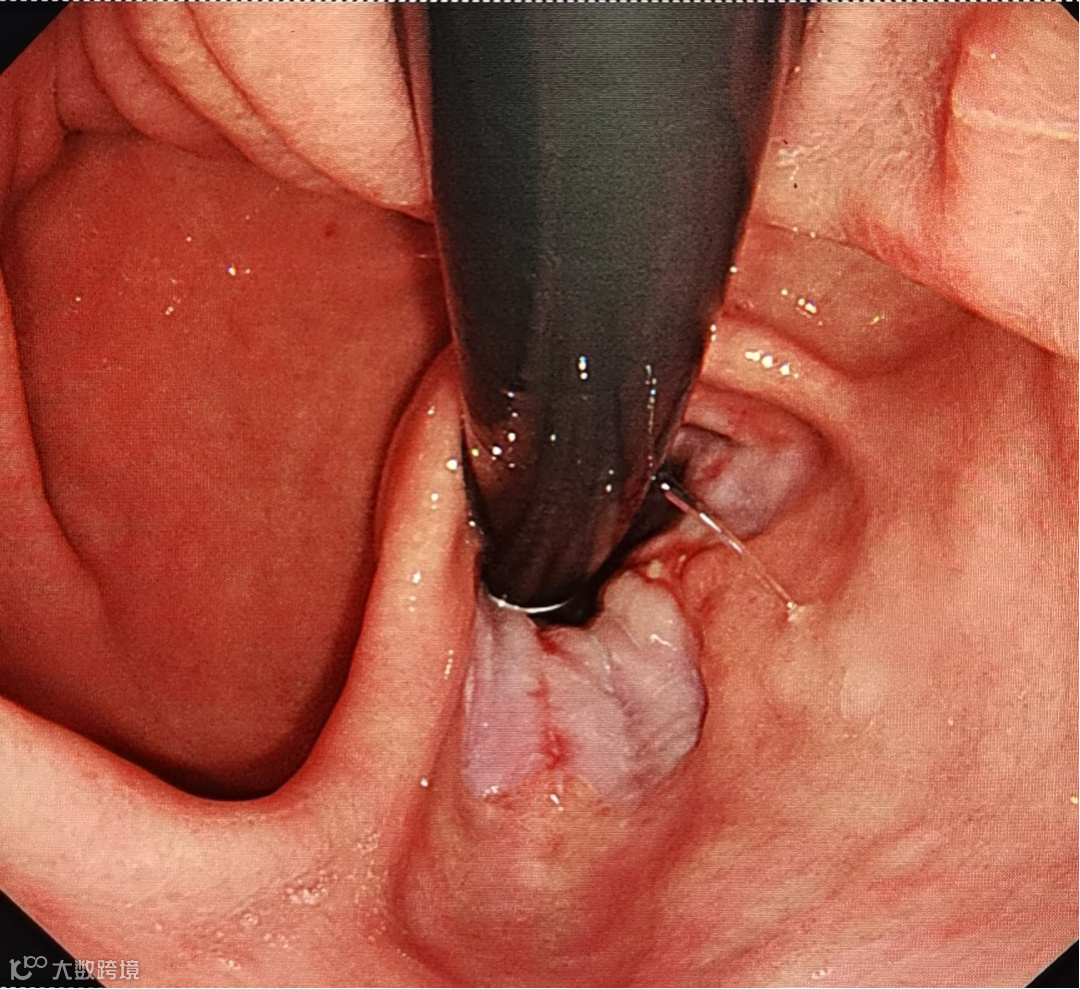

术中照片(点击查看)

武海军主任团队采用了先进的腹腔镜技术,手术过程中,仅在张女士的腹部做了几个小切口(直径约1CM),通过其中一个切口插入腹腔镜,这个小小的镜头如同医生的“眼睛”,就能通过视频监控器清晰地观察到不同角度疝的情况。随后,通过其他切口插入手术器械,在视频监视下,精准地对疝进行了修补。